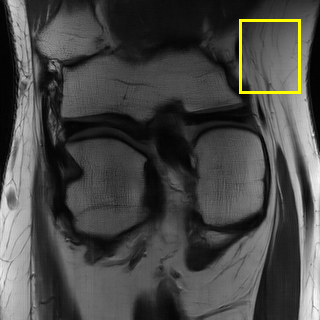

Edge preserving has always been a crucial concern in the design of reconstruction models. To improve the quality of reconstructed images and preserve image edges, some works suggested introducing edge priors in the original restoration problem to preserve image edges [4, 34]. However, they will suffer from complicated algorithm design and time-consuming training processes. Recently, some more efficient methods have been proposed to use edge maps as external guidance for image restoration. For example, Yang et al. [48] used off-the-shelf edge detectors to extract image edges from the degraded images. Fang et al. [12] predicted image edges by constructing an edge reconstruction network. Huang et al. [18] designed a novel dual discriminator GAN framework for solving fast multi-channel MRI, in which one GAN network is built for edge information enhancement. Inspired by these methods, we also consider introducing image edge prior as external guidance to MRI reconstruction since 1) image edges are prominent and distinguishable features in MRI (see Fig. 1), which can serve as a good guide to the model to recover high-frequency details; 2) the ground truth edges can be easily fetched via ordinary edge extraction operators, like Canny, Sobel, and Prewitt, which means that the edge maps can be learned in a data-driven manner. However, how to effectively utilize image edge priors to guide image reconstruction still remains a challenge. In some methods, edge information was simply concatenated with the input image and passed to the next stages. Though this is a simple way to utilize the edge priors, it may not give full play to the guiding role of the edge priors. Therefore, in this work, we want to explore a more efficient and effective mechanism to fully take advantage of image edge priors.

(a)

(b)

(c)

fastMRI is a large-scale MR dataset jointly established by Facebook AI Research and NYU Langone Health. It provides both knee and brain datasets for evaluation. In our work, we use the multi-coil knee dataset, which was acquired on three clinical 3T systems or one clinical 1.5T system using a 15-channel knee coil array. The dataset includes data from two pulse sequences, yielding coronal proton-density weighting with (PDFS) and without (PD) fat suppression. As is shown in Fig. 1, PD images usually contain more structural and prominent edge features than PDFS images, which suggests that it is more challenging to use edge guidance on PDFS datasets. Therefore, we explore the effectiveness of EAMRI on these two modalities. Following [13], for both PD and PDFS knee datasets, we separately filter out 227 volumes (8332 slices) for training and 24 volumes (1665 slices) for testing. The dataset is centrally cropped to .